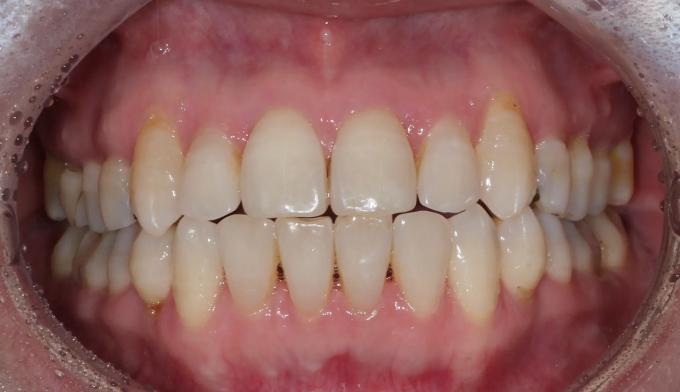

덧니

교정치료에 나이 제한은 없습니다.

건강한 잇몸을 가지고 있다면 60,70대에도 전혀 문제없고, 잇몸이 건강하지 못하다면 20대여도 교정이 힘들 수 있습니다.

아무래도 나이가 있으면 세포활성이 떨어지고 피부의 탄력도 줄어들기 마련입니다.

따라서 섣불리 발치교정을 진행하여서는 안됩니다. 오히려 교정후에 더 나이들어 보이는 경우가 생길 수 있기 때문입니다.

비발치교정을 통하여 치아를 배열하고 일부러 앞니를 조금 더 앞으로 이동시켜 깊어진 팔자주름을 옅게 만들어주었습니다.